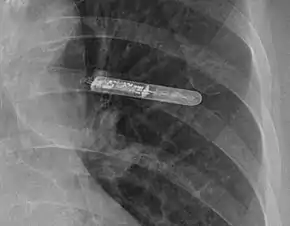

An implantable loop recorder (ILR), also known as an insertable cardiac monitor (ICM), is a small device that is implanted under the skin of the chest for cardiac monitoring, to record the heart's electrical activity for an extended period.[1]

The ILR is implanted by an electrophysiologist under local anesthesia. A small incision (about 3–4 cm or 1.5 inches) is made just lateral to the sternum below the nipple line, usually on the patient's left side.[6] A pocket is created under the skin, and the ILR is placed in the pocket. Patients can go home the day of the procedure with few restrictions on activities.[4] Bruising and discomfort in the implant area may persist for several weeks.